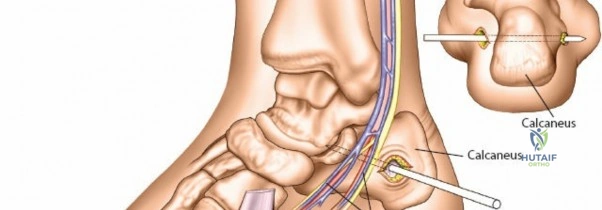

Wrist spanning fixators are the workhorse for highly comminuted distal radius fractures or radiocarpal fracture-dislocations.

Metacarpal Pin Placement

1. Make two 1 cm incisions over the dorsoradial aspect of the second metacarpal.

2. Dissect bluntly, protecting the dorsal sensory branches of the radial nerve and the extensor tendons.

3. Place the tissue sleeve at a 45-degree angle to the dorsal and lateral planes to maximize purchase in the metacarpal shaft.

4. Pre-drill and insert two 3.0 mm pins.

Proximal Radius Pin Placement

1. Make incisions over the dorsolateral aspect of the radius, approximately 10-12 cm proximal to the radiocarpal joint.

2. Dissect bluntly to avoid the SRN.

3. Insert two 4.0 mm pins.

Construct Assembly and Reduction

Connect the metacarpal pins and the radius pins with a multi-pin clamp or individual pin-to-bar clamps. Apply longitudinal traction to utilize ligamentotaxis to restore radial length and radial inclination. Volar tilt is often restored by translating the distal fragment or applying a slight volar directed force before tightening the frame. Confirm reduction with PA and lateral fluoroscopy.